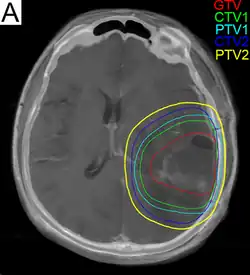

.png)

Subsequent to surgery, radiotherapy becomes the mainstay of treatment for people with glioblastoma. It is typically performed along with giving temozolomide.[10] A pivotal clinical trial carried out in the early 1970s showed that among 303 GBM patients randomized to radiation or best medical therapy, those who received radiation had a median survival more than double those who did not.[78] Subsequent clinical research has attempted to build on the backbone of surgery followed by radiation. Whole-brain radiotherapy does not improve when compared to the more precise and targeted three-dimensional conformal radiotherapy.[79] A total radiation dose of 60–65 Gy has been found to be optimal for treatment.[80]

GBM tumors are well known to contain zones of tissue exhibiting hypoxia, which are highly resistant to radiotherapy. Various approaches to chemotherapy radiosensitizers have been pursued, with limited success as of 2016. As of 2010, newer research approaches included preclinical and clinical investigations into the use of an oxygen diffusion-enhancing compound such as trans sodium crocetinate as radiosensitizers,[81] and as of 2015 a clinical trial was underway.[82] Boron neutron capture therapy has been tested as an alternative treatment for glioblastoma, but is not in common use.